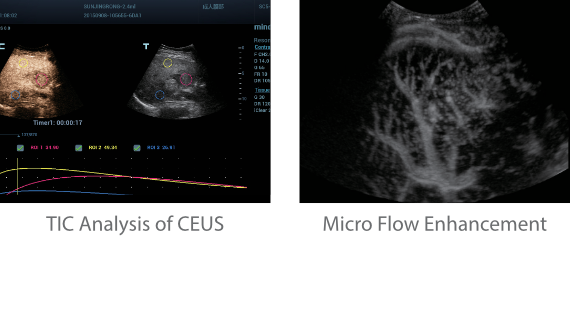

Since the company was founded, Mindray has been continuously exploring new ways to improve diagnostic confidence. Powered by the most revolutionary ZONE Sonography? Technology, Resona 7ŌĆÖs new ZST+ platform brings ultrasound image quality to a higher level by zone acquisition and channel data processing.

As well as the premium level image quality, Resona 7 also enhances clinical research capabilities with the revolutionary V Flow for vascular hemodynamic evaluation, and the most intelligent plane acquisition from 3D datasets for fetal CNS diagnosis. Combining the most intuitive gesture-based multi-touch operation and all the essential clinical features, Resona 7 is truly leading new waves in ultrasound innovation.